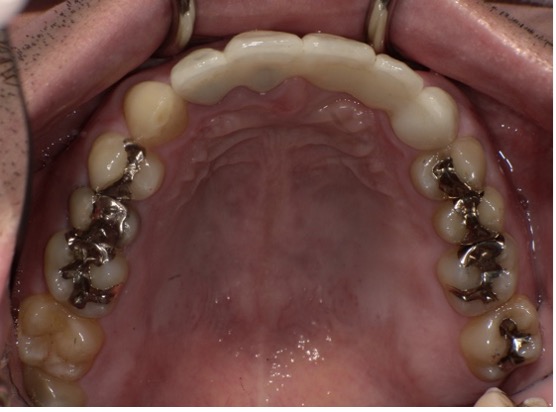

【After】

インプラントを左右の奥歯に入れたことで左右のバランスが良くなり、前歯の噛み合わせも改善されたことで全体的に調和の取れた噛み合わせをつくる事ができました。